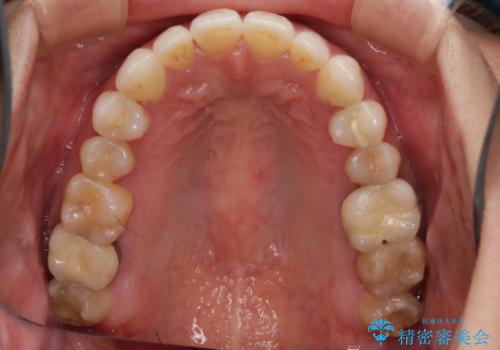

- 前歯のがたつきと反対咬合を主訴に来院されました。

インビザライン・クリンチェック(歯のシミュレーション)を行い、

インビザラインライトで治せる範囲であることを確認し治療を開始することになりました。

今回はクリンチェックを作成したのちに、枚数が少なくても可能であることが判明したためインビザラインライトでの治療を行いました。

最初はインビザラインモデレートパッケージの予定で契約をされていたので、金額も10万円以上安くなり仕上がりも満足頂きました。